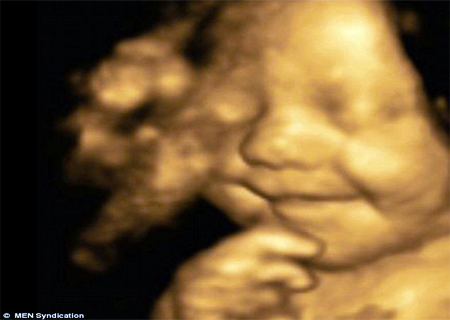

Bebê mais feliz do mundo sorri no ultrassom

O bebê Leo Hargreaves já ganhou vários admiradores por causa do seu sorriso, que começou quando era um feto e apareceu todo feliz nas fotos do ultrassom 4D.

Hoje ele está com 5 meses e mantém a mesma expressão feliz da época em que estava na barriga da mamãe, Amy Cregg, de 31 anos.

O ultrassom foi feito quando Amy estava na 31ª semana de gestação, ou sétimo mês.